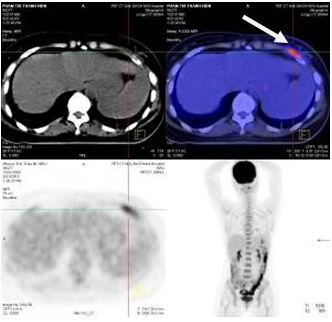

Hình 2: Hình ảnh chụp cắt lớp vi tính lồng ngực: Tổn thương dạng khối thùy trên phổi trái kích thước 1 x 2 cm, tổn thương thùy dưới phổi trái kích thước 0,5 x 0,7 cm.

Hình 6: Hình ảnh PET/CT sau một chu kỳ hóa chất: Tổn thương xẹp đốt sống D7 không hấp thu FDG (mũi tên đỏ), tổn thương cung trước xương sườn VI (mũi tên trắng)